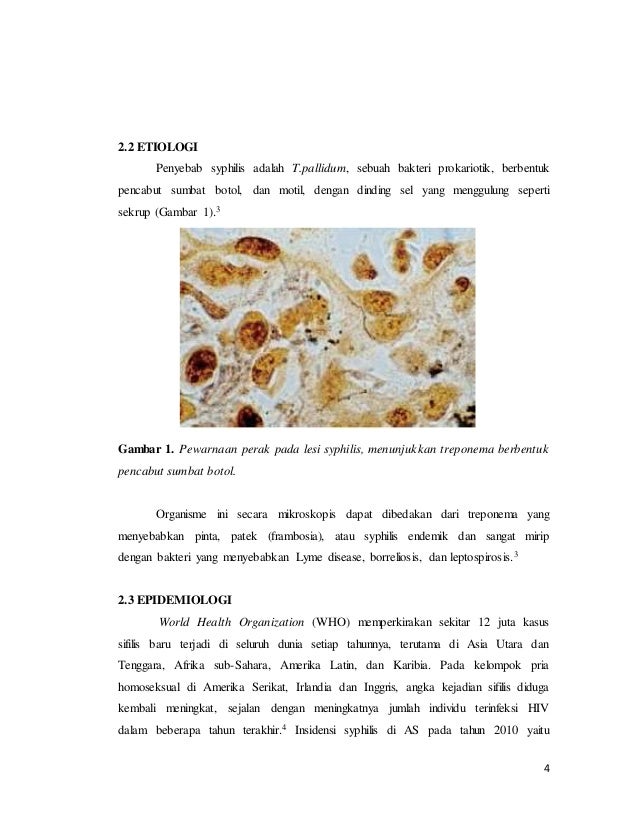

5 BAB II TINJAUAN PUSTAKA A. Sifilis Sifilis adalah penyakit menular seksual yang ditandai dengan adanya lesi primer kemudian di

BAB 2 TINJAUAN PUSTAKA 2.1. Penyakit Sifilis Sifilis adalah

BAB 2 TINJAUAN PUSTAKA 2.1. Penyakit Sifilis Sifilis adalah